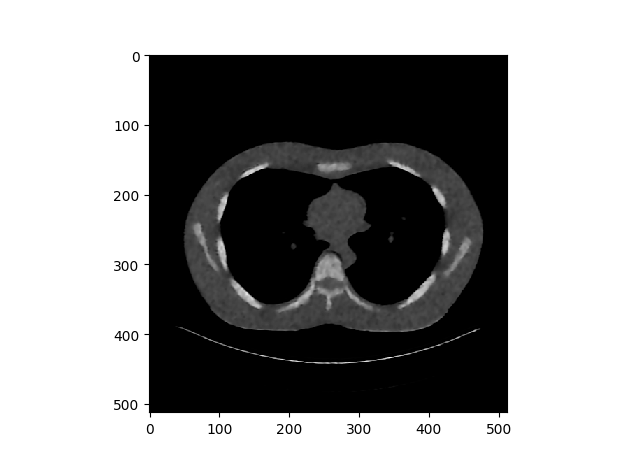

Results (Dilated Back Propagation)

Left → Original Lung CT Scan Image

Middle → Contaminated Image with uniform distribution noise

Right → Denoised Image

For manual back propagation, the images did not have spaces filled up.

Close Up Look

Left → Original Image

Middle → Resulted Image from Auto Differentiation

Right → Resulted Image from Dilated Back Propagation

When we see the closed up view of each images, we can clearly see most of the sharp edge details are gone. Hence the saga continues……